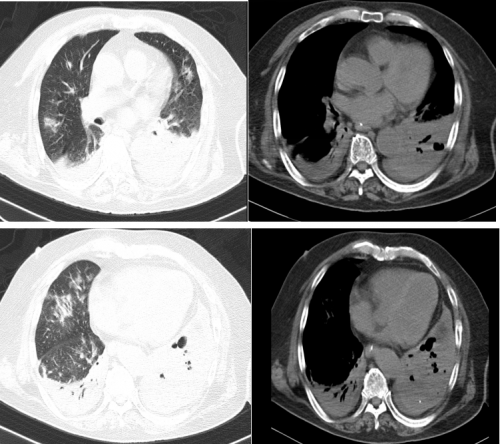

10-20胸部CT:

10-22:真菌培养:黄蓝状菌(蠕行青霉 )1cfu